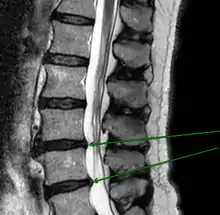

Механическое смещение одного из поясничных позвонков, переохлаждение, локальная инфекция, опухоли, деградация тканей, могут привести к воспалительному процессу в позвоночно-двигательном сегменте, последующим мучительным болям, вынужденным положениям тела. Очень распространённой причиной патологии в поясничном отделе позвоночника является неверное распределение нагрузки на поясничный отдел позвоночника, когда дополнительный вес (а иногда и собственный вес) поднимаются с единственным рычагом в поясничном отделе позвоночника. Частым заболеванием в поясничном отделе позвоночника являются грыжи межпозвоночных дисков — выпячивания пульпозного ядра диска за пределы его фиброзного кольца. В 48 % случаев межпозвоночные грыжи локализуются на уровне L5-S1 пояснично-крестцового отдела, в 46 % случаев — на уровне L4-L5, и лишь в оставшихся 6 % случаев — между другими позвонками поясничного, шейного или грудного отделов позвоночника.